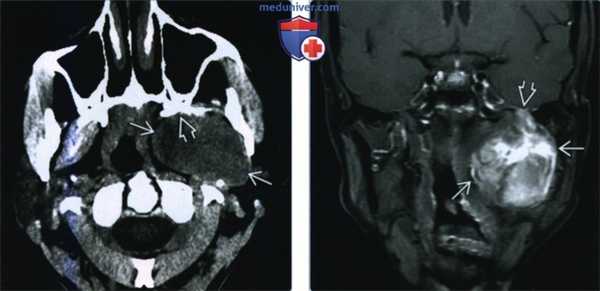

(Слева) МРТ Т1ВИ в аксиальной проекции, пациент, которому ранее проводилось лечение по поводу плоскоклеточного рака носоглотки. Костный мозг в правой ветви нижней челюсти замещен опухолевой тканью, на уровне отверстия нижней челюсти также определяется патологическая ткань, появление которой связано с распространением опухоли по нижнечелюстному нерву. Обратите внимание на нормальный костный мозг левой ветви нижней челюсти, который имеет гиперинтенсивный сигнал.

(Справа) МРТ Т1ВИ в аксиальной проекции, этот же пациент. Периневральное распространение опухоли по нижнечелюстному нерву с облитерацией жировой клетчатки жевательного пространства.

(Слева) МРТ Т1ВИ с КУ, коронарная проекция, этот же пациент. По нижнечелюстному нерву опухоль распространяется в овальное отверстие и тройничную полость. Также опухоль прорастает латеральнее, в твердую мозговую оболочку средней черепной ямки.

(Справа) КТ с КУ в аксиальной проекции, этот же пациент. В области правого отверстия нижней челюсти определяется накапливающая контраст опухоль. В жевательном пространстве видны участки аномального накопления контраста вдоль волокон нижнечелюстного нерва.

(Слева) КТ в костном окне, аксиальная проекция. По сравнению с нормальным левым овальным отверстием правое овальное отверстие увеличено в размерах. Расширение отверстия обусловлено распространением злокачественной опухоли по нижнечелюстному нерву.

(Справа) КТ с КУ, аксиальная проекция. По волокнам нижнечелюаного нерва опухоль распространилась в тройничную полость и среднюю черепную ямку. Обратите внимание, что с левой стороны тройничная полость имеет нормальную плотность, соответствующую плотности спинномозговой жидкости.